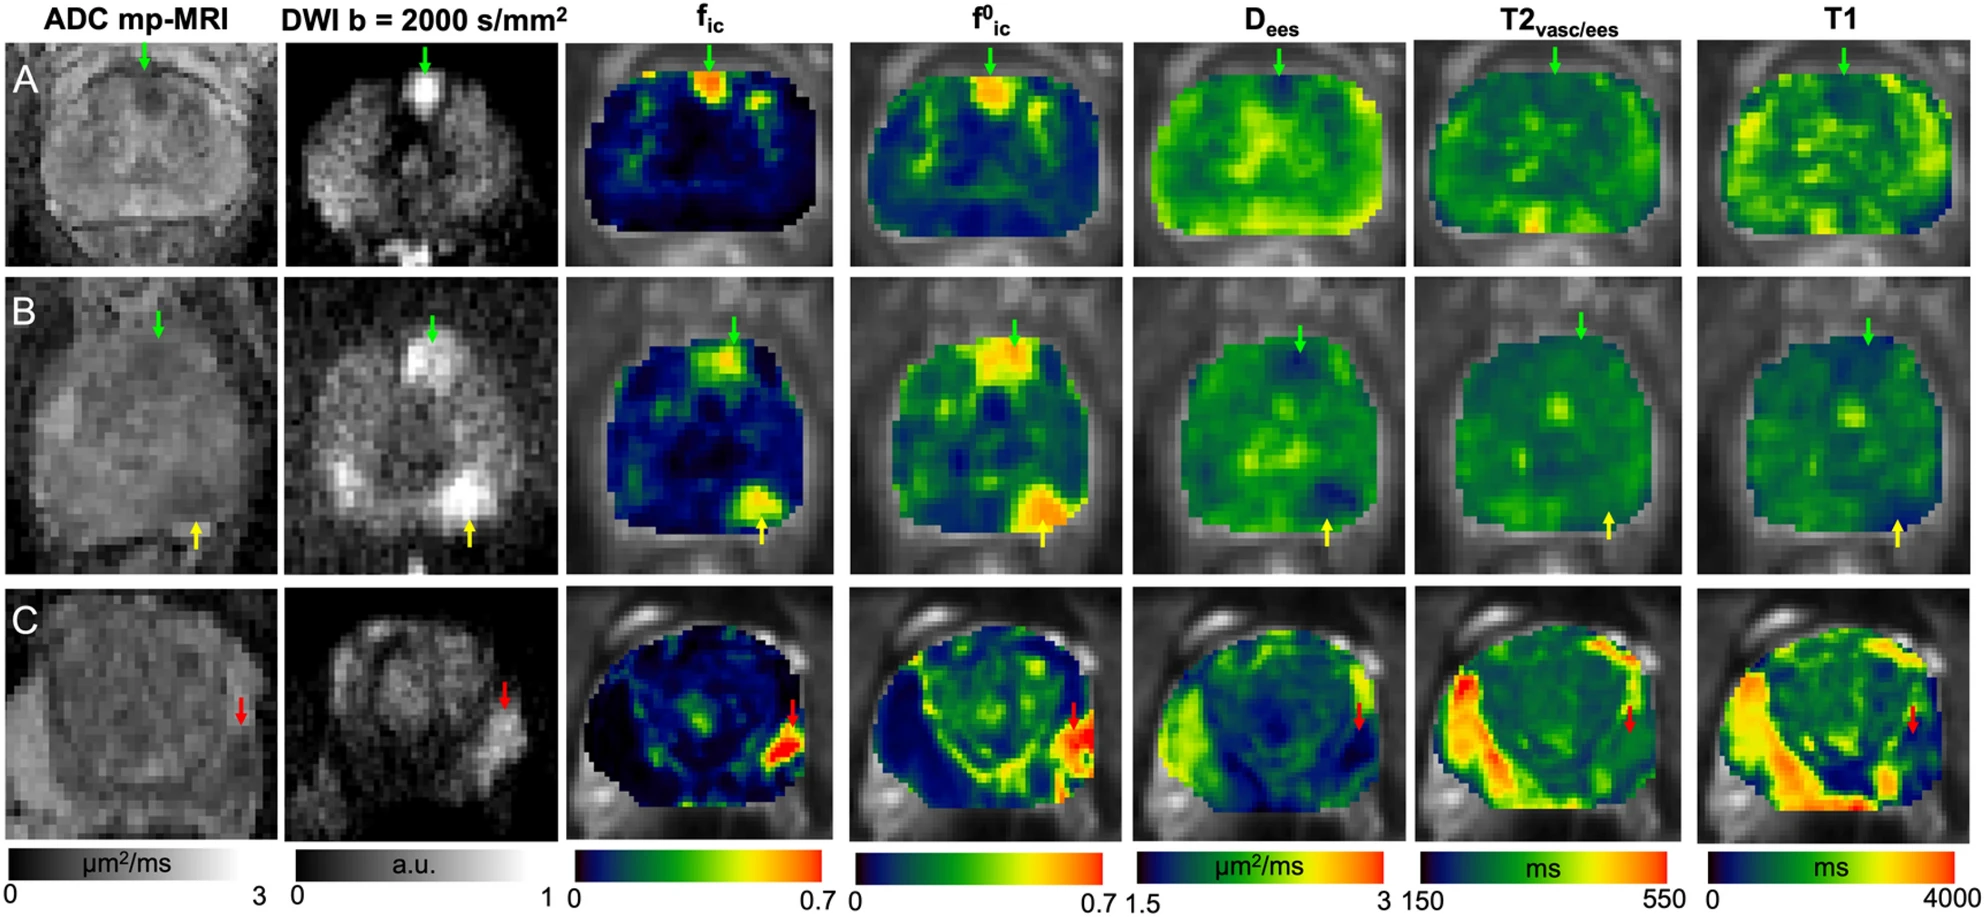

VERDICT (Vascular, Extracellular, and Restricted DIffusion for Cytometry in Tumours) is a diffusion MRI framework for the characterisation of different components of tumours, which has shown diagnostic utility for body cancer. The aim of this study was to extend the VERDICT framework to comprehensively characterise brain tumours, which is challenging due to the complexity of brain tissues. The resulting biomarkers showed agreement with histology and followed the expected trends when comparing different tumour types and sub-regions. These preliminary results hold promise for the non-invasive characterisation of brain tumours by VERDICT-MRI, which would be an important tool for diagnosis and monitoring of treatment effects.

Matteo Figini,Antonella Castellano,Michele Bailo,Marcella Callea, Marcello Cadioli, Marcello Cadioli, Samira Bouyagoub, Marco Palombo, Valentina Pieri, Pietro Mortini, Andrea Falini, Daniel C. Alexander, Mara Cercignani and Eleftheria Panagiotaki